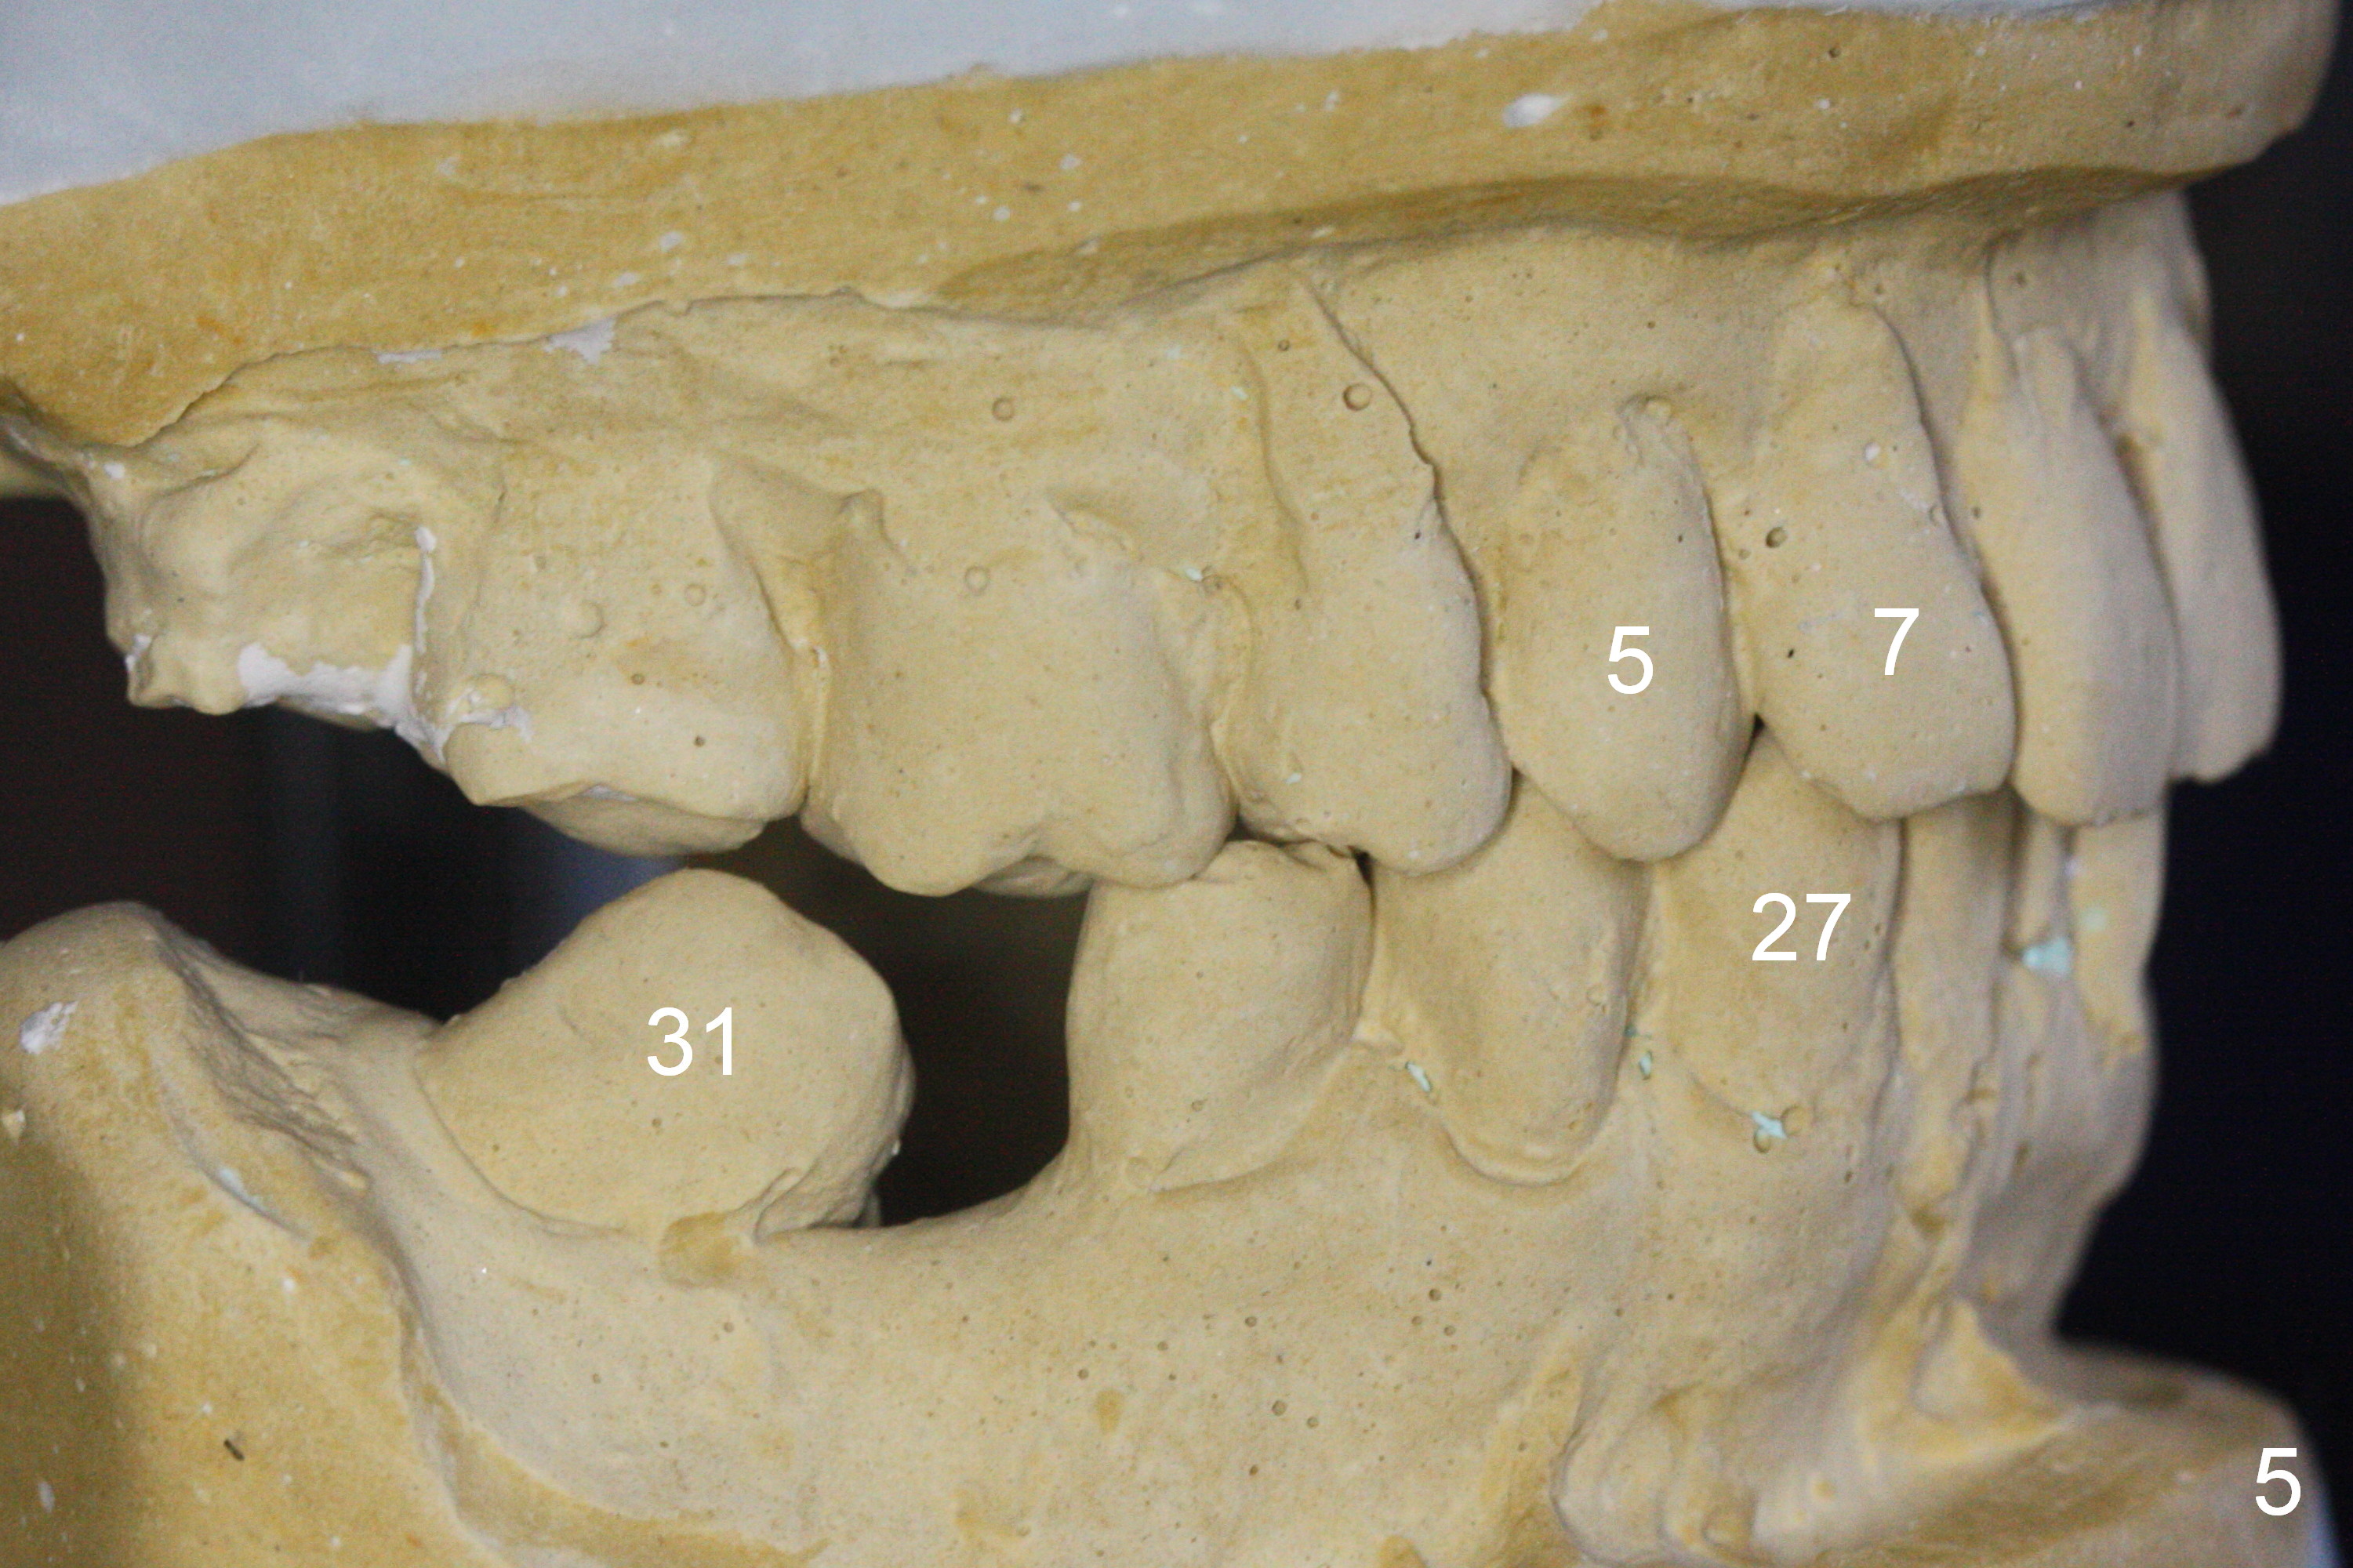

A 82-year-old man has pain in the lower left bridge. There is a buccal apical fistula associated with the tooth #17 (Fig.1). An immediate implant will be placed at #17 after bridge removal (Fig.2,3 blue). Once it osteointegrates, it will be used an anchorage (direct (instead of indirect), most efficient) to upright the tooth #18 (change the longitudinal axis from red line to purple one (Fig.4); white circle: center of resistance (rotation)). Then an implant will be placed at #19 (white rectangle).

Take Alginate impression and keep it moist. It will be used as a stent for temporization later on. After the tooth #17 is extracted with Clindamycin treatment, a FC dummy implant (5x9 mm) will be placed, followed by 6x4(2) mm abutment (Fig.3,4 pink). If there is severe vertical height issue, change to Magicore. Due to schedule conflict, prepare UF for this case instead.

One of the patient's daughter feels that the treatment is too complicated. She would like to have the 2nd molars extracted and implants at the 1st and 2nd molar sites (from Fig.5,6 to 7-9). Since the upper canines are missing (Fig.5,6), the final occlusion will be Class II posteriorly (Fig.8,9).